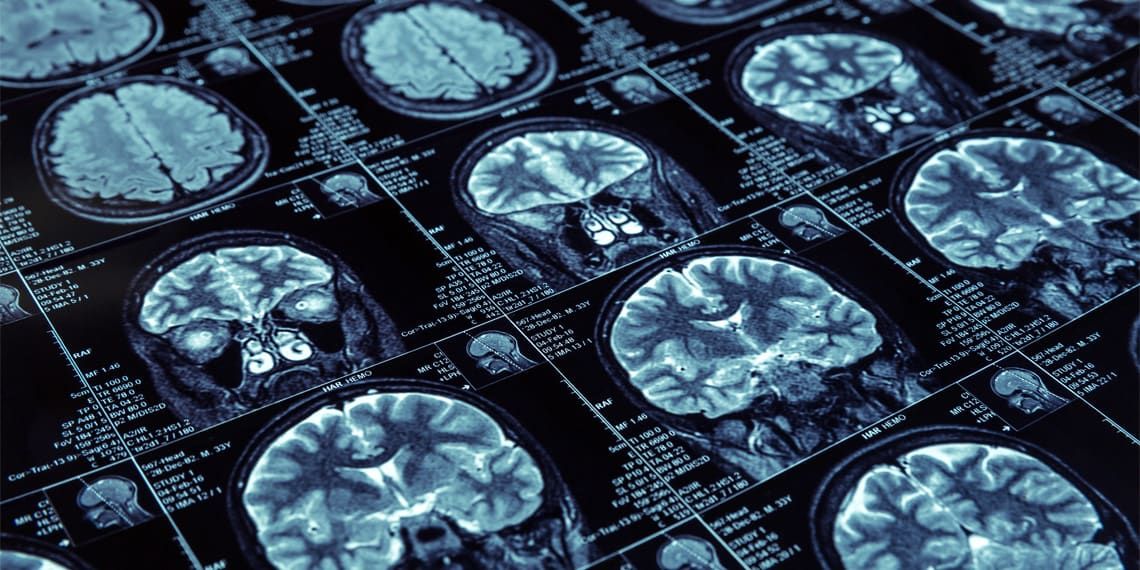

A neuroimaging study conducted in the Netherlands on individuals with depression has identified brain networks linked to specific cognitive functions. It was further discovered that those with more severe depression symptoms generally exhibit weaker connectivity in the brain network associated with cognitive processing speed. The study was published in Psychological Medicine. Major Depressive Disorder (MDD), commonly referred to as depression, is a severe mental health condition characterized by a pervasive and prolonged sense of sadness, hopelessness, and a lack of interest or pleasure in act...